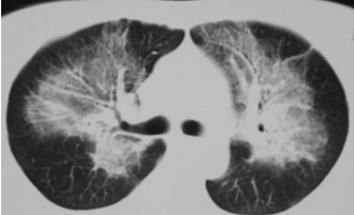

2.青年男性,平素体健,近2日诉咳嗽、气促、发热,CT如下:

病灶沿着肺门分布,略呈蝴蝶状,心源性肺水肿?没有心脏病,这么年轻,没道理啊,再说了,心衰怎么就发热了?

追问病史,在厂里反应炉气体泄漏后发病,结合工作环境,考虑有机氟中毒性肺水肿。